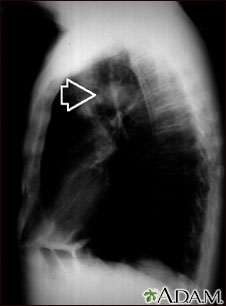

Pulmonary mass - side view chest x-ray

This individual has a mass in the upper part of the lung. Although the cause of the mass can be suspected, based on this person's history, there are many diseases that can produce lung lesions.